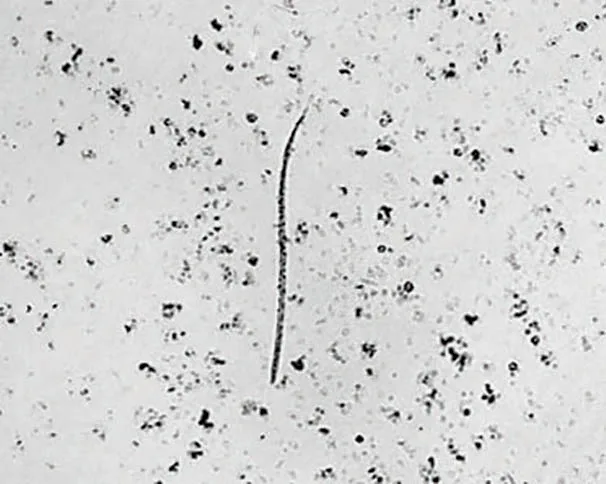

FIGURE 2

Single microfilaria in a blood smear